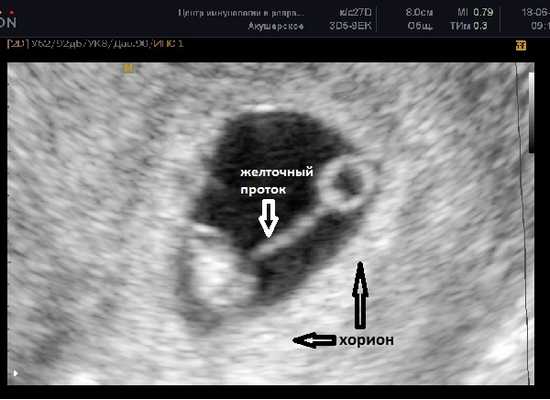

7 - 8 недель

Фото УЗИ плода при беременности 7-8 недель

Расстояние между эмбрионом и желточным мешком постепенно увеличивается и становится хорошо различим желточный проток (ductus vitellinus), соединяющий между собой желточный мешок и кишечник эмбриона. Так же, как и желточный мешок, проток на более поздних сроках запустевает и рассасывается, но если это не происходит по каким-то причинам, то у человека формируется слепое выпячивание стенки подвздошной кишки - дивертикул Меккеля.

До этого срока хорион имеет кольцевидную форму, окружает плодное яйцо со всех сторон и пока ещё нельзя сказать к какой стенке матки прикрепился эмбрион.

В случае монохориальной двойни ещё не видно амниотических оболочек и при наличии двух желточных мешков всё ещё нельзя сказать является ли данная беременность моно или диамниотической. Если плодное яйцо содержит два желточных мешка и два плода с наличием сердечной активности, в последующем количество амниотических полостей может быть больше, чем количество плацент (монохориальная диамниотическая) или одинаковым (монохориальная моноамниотическая). В этом случае точно определить амниональность возможно после 8 недель, когда амниотические оболочки начинают четко визуализироваться.

ЧСС эмбриона 130-160 ударов в минуту.

СВД плодного яйца 24-30 мм, КТР эмбриона 9-15 мм.